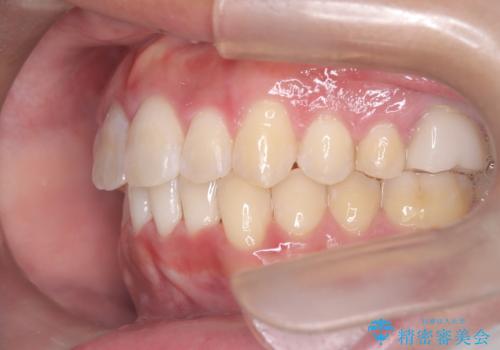

【インビザライン 非抜歯】歯の捻じれと歯のでこぼこを治したい!

- 「上の前歯の捻じれと下の前歯のでこぼこを治したい」を主訴に来院された患者様です。

矯正検査の結果、非抜歯で矯正可能だったためインビザラインで治療を行いました。

アーチの拡大とIPRで叢生を改善いました。

11ヵ月で矯正を終える事ができ患者様も大変ご満足されていました。